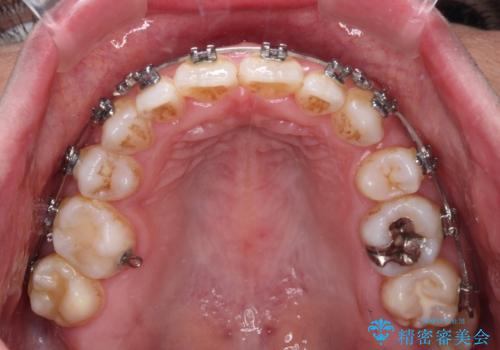

- メタルブラケット

バランスを取るために右下と左上の小臼歯を1本ずつ抜歯し、移動のための固定源としてアンカースクリューを利用してワイヤー装置による矯正治療を行うこととしました。

骨格的な左右差があり、上下正中をぴったり合わせることは難しく、奥歯の咬み合わせの調整にも時間がかかりましたが、きれいに整えることができました。